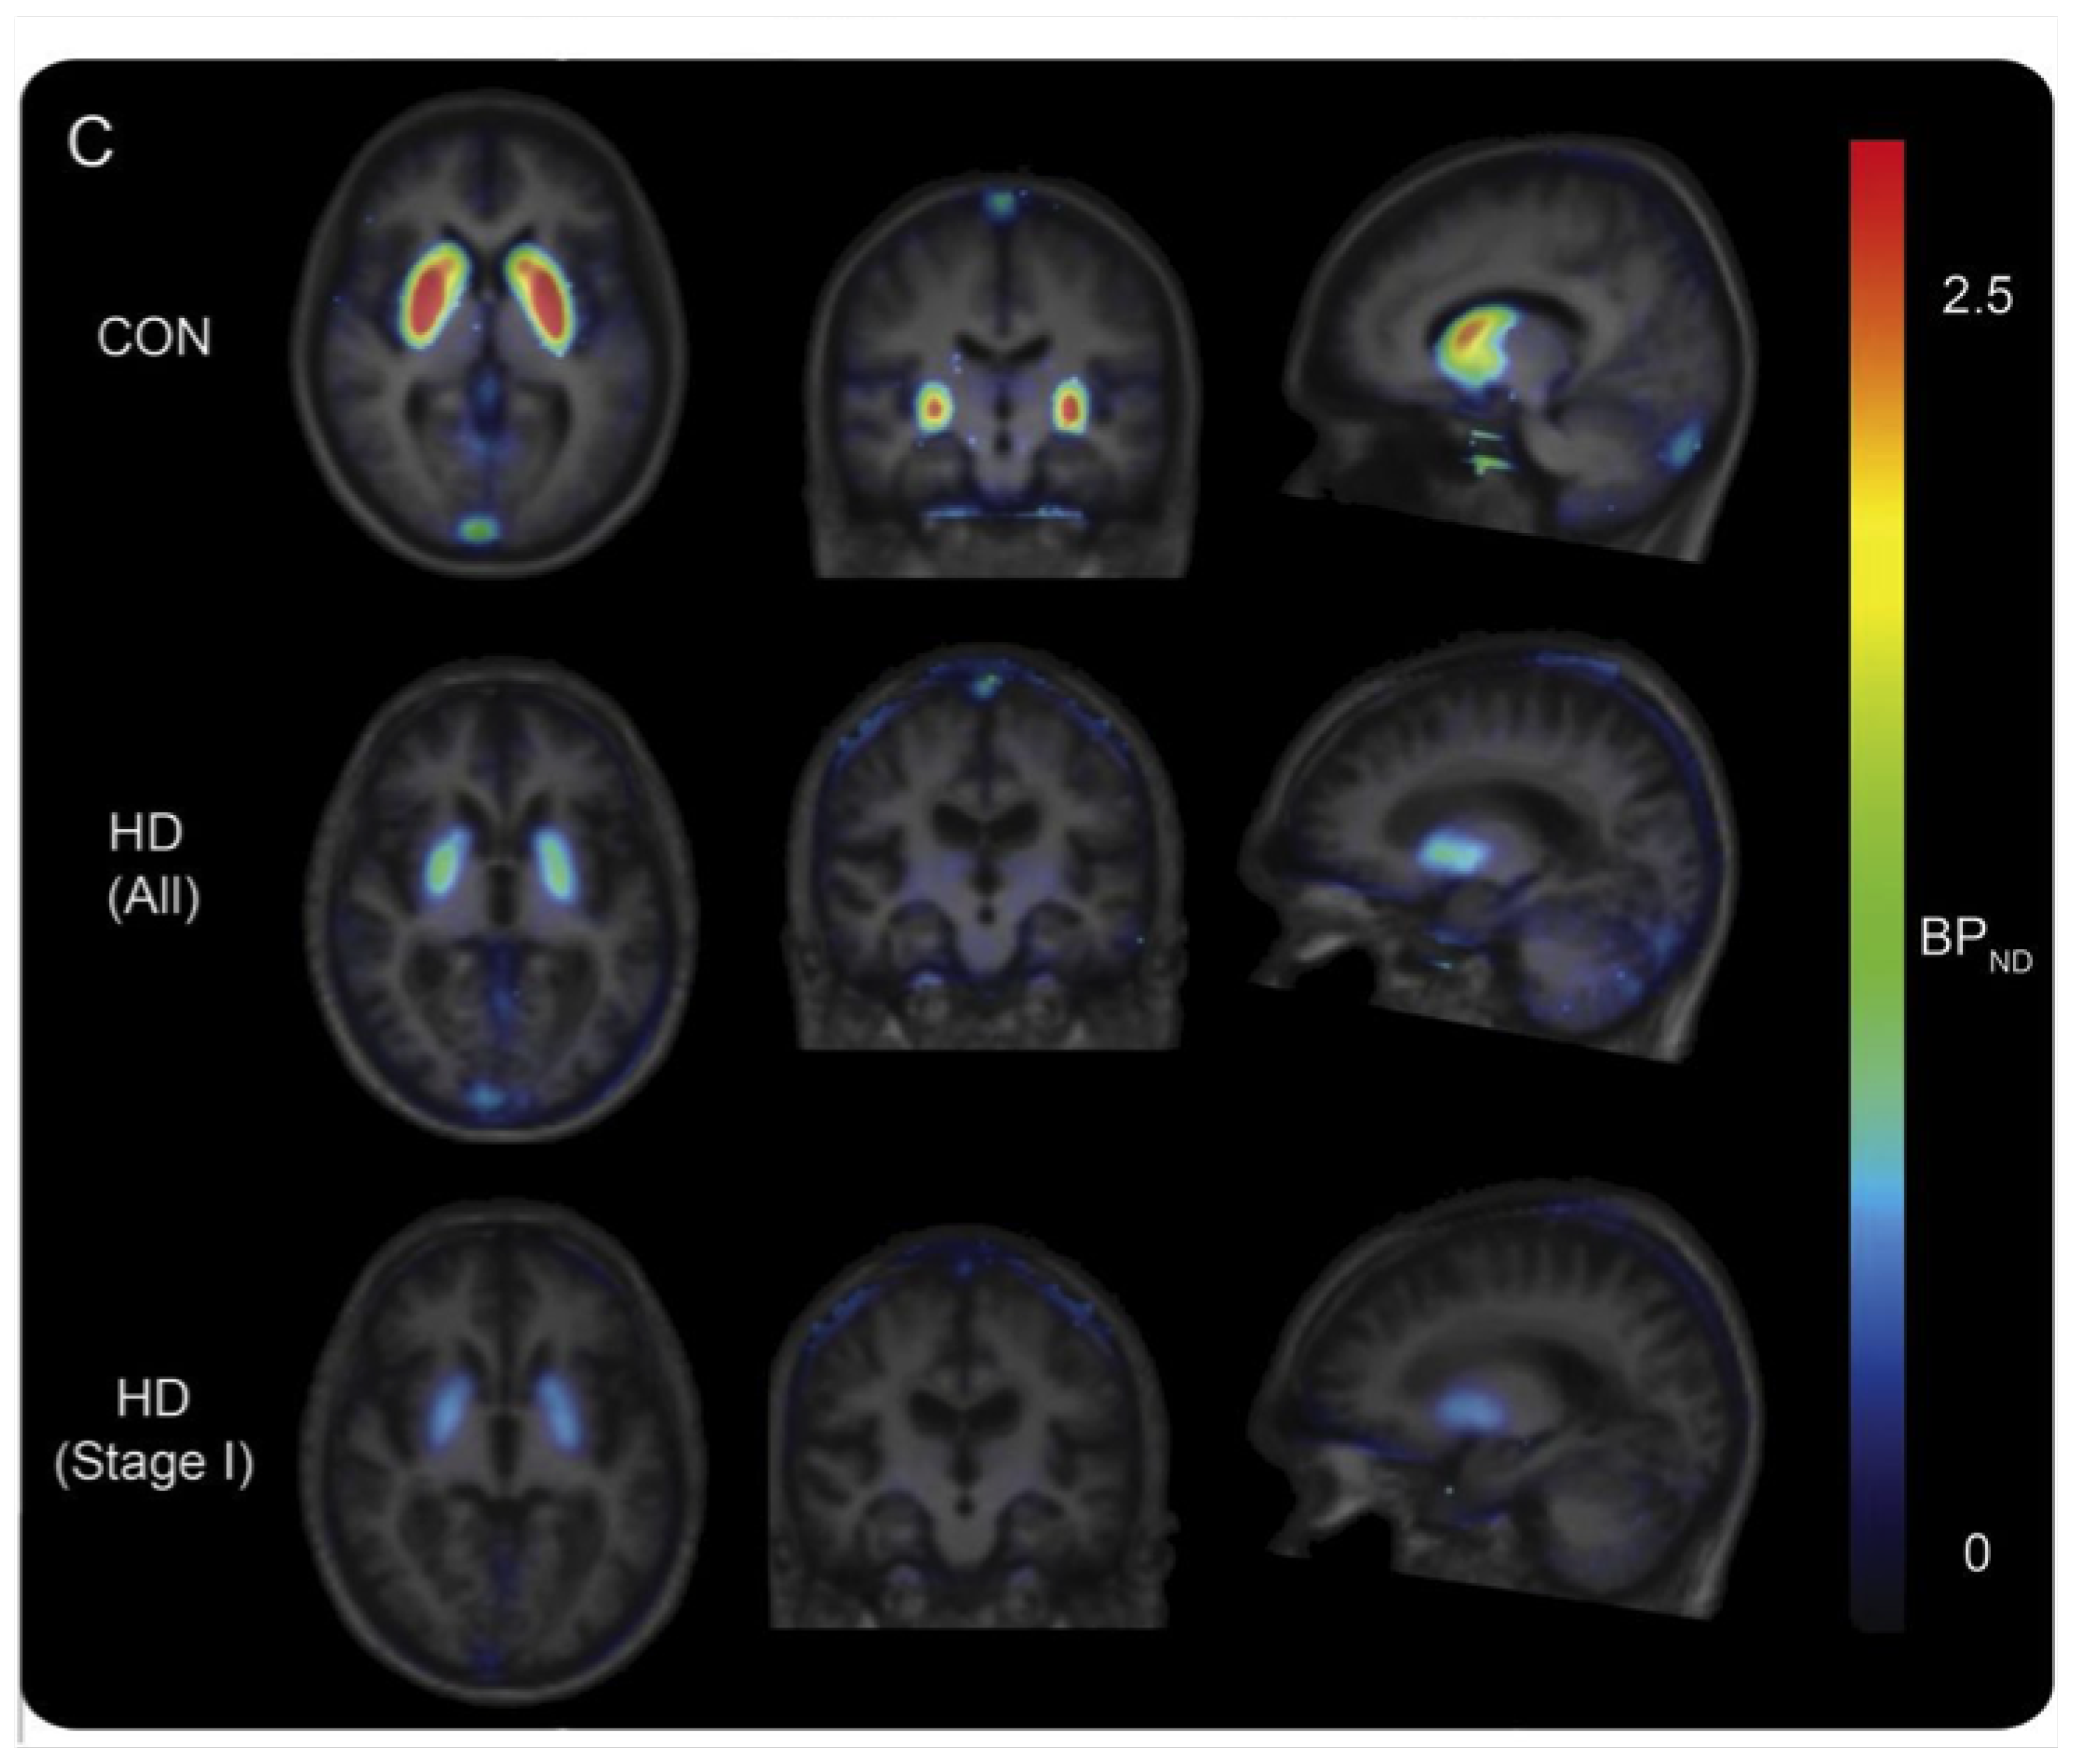

- Van Laere, K.; Casteels, C.; Dhollander, I.; Goffin, K.; Grachev, I.; Bormans, G.; Vandenberghe, W. Widespread Decrease of Type 1 Cannabinoid Receptor Availability in Huntington Disease In Vivo. J. Nucl. Med. 2010, 51, 1413–1417. [Google Scholar] [CrossRef]